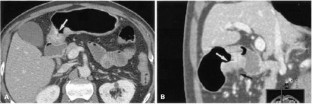

Figure 3